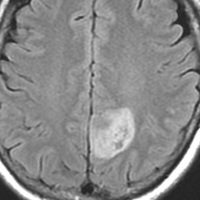

小児の良性の神経節膠腫 ganglioglioma グレード1(真の腫瘍)

7才の時に音読でつかえるようになり,眼で何かを追っているような欠伸発作(左側頭葉てんかん)を繰り返すようになり,強直間代発作を生じて腫瘍が発見されました。下側頭回底面の皮質に発生した境界明瞭な腫瘍であり,周囲に脳浮腫を伴っています。T2強調画像で線維成分の多い硬い部分は低信号に,軟らかい部分はやや高信号となり,ガドリニウムでheterogenousに増強されます。グレード1の神経節膠腫としては非典型的な画像所見で術前診断は難しいもので,PXA pleomorphic xanthoastrocytoma も疑いました。もちろん治療としては開頭手術での全摘出です。術後に発作は消失しています。

構成要素はGFAP陽性の膠細胞が多く認められます。神経細胞様形態の細胞 ganglion cellではNeuN(+), CGA (+) synaptophisin (++), neurofilament (+)です。大型で腫大した核を有して核内封入体構造を有する好酸性もしくは淡明な細胞質を有する細胞が増殖してPXAを考えさせる部分像もありました。granular bodyも認められて,右の写真のように膠原線維の増生が目立つ部分もあります。これは表面の非常に硬い線維性の腫瘍部分です。MIB-1 indexは4%とやや高い値です。BRAF v600Eの変異が認められました。